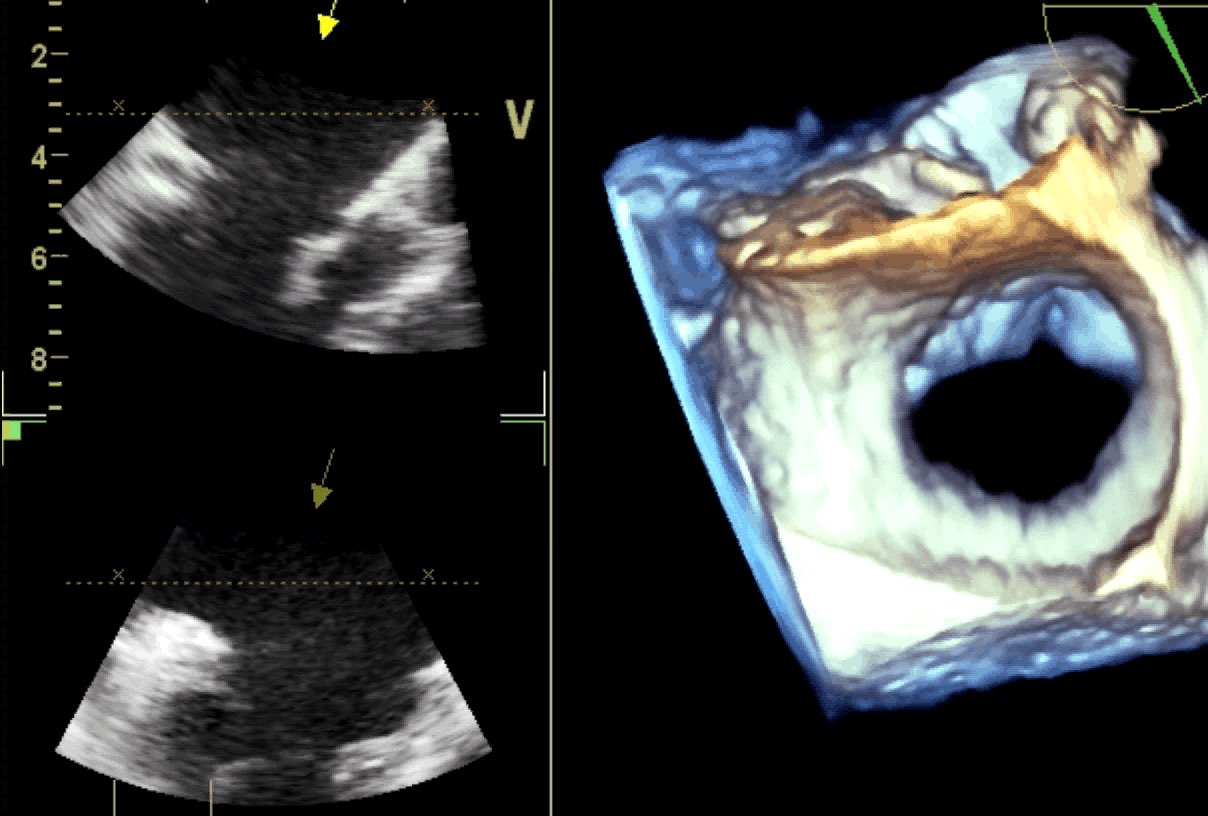

Protesi mitralica meccanica normofunzionante

Daniela Torta